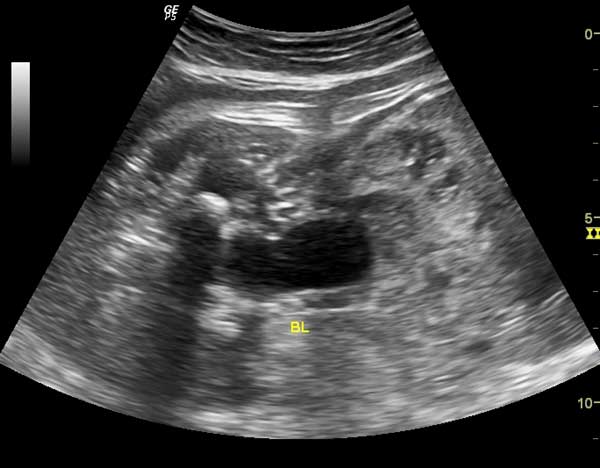

This 53 year-old woman has a uterine lesion and irregular bleeding. Which of the following is the correct diagnosis?